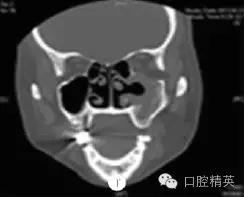

鼻竇CT檢查示:右側(cè)尖牙牙根處有一類(lèi)圓形軟組織密度影(圖a),病變向上進(jìn)入右側(cè)上頜竇,其內(nèi)見(jiàn)弧形線狀高密度影,鄰近牙槽骨壓迫性骨吸收(圖b)??紤]為根尖囊腫并發(fā)感染(右)。

圖a:術(shù)前水平位CT檢查顯示右側(cè)上頜竇黏膜囊腫,中央有類(lèi)圓形影;圖b:術(shù)前冠狀位CT檢查顯示右側(cè)上頜竇黏膜囊腫并根尖骨質(zhì)吸收,含類(lèi)圓形影;